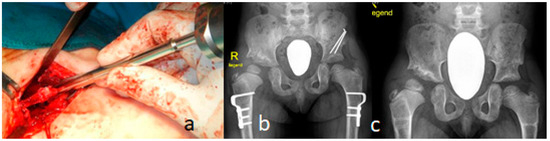

Figure 6.

(a–c): A double incision was used for this type of surgery in a 14-month-old girl with Larsen syndrome (a). Proximal femoral osteotomy for varization osteotomy and de-rotation was performed at the intertrochanteric level (b). In the postoperative period, neck-shaft angles were never reduced to less than 110°, and the de-rotation angle was less than 20° (c).